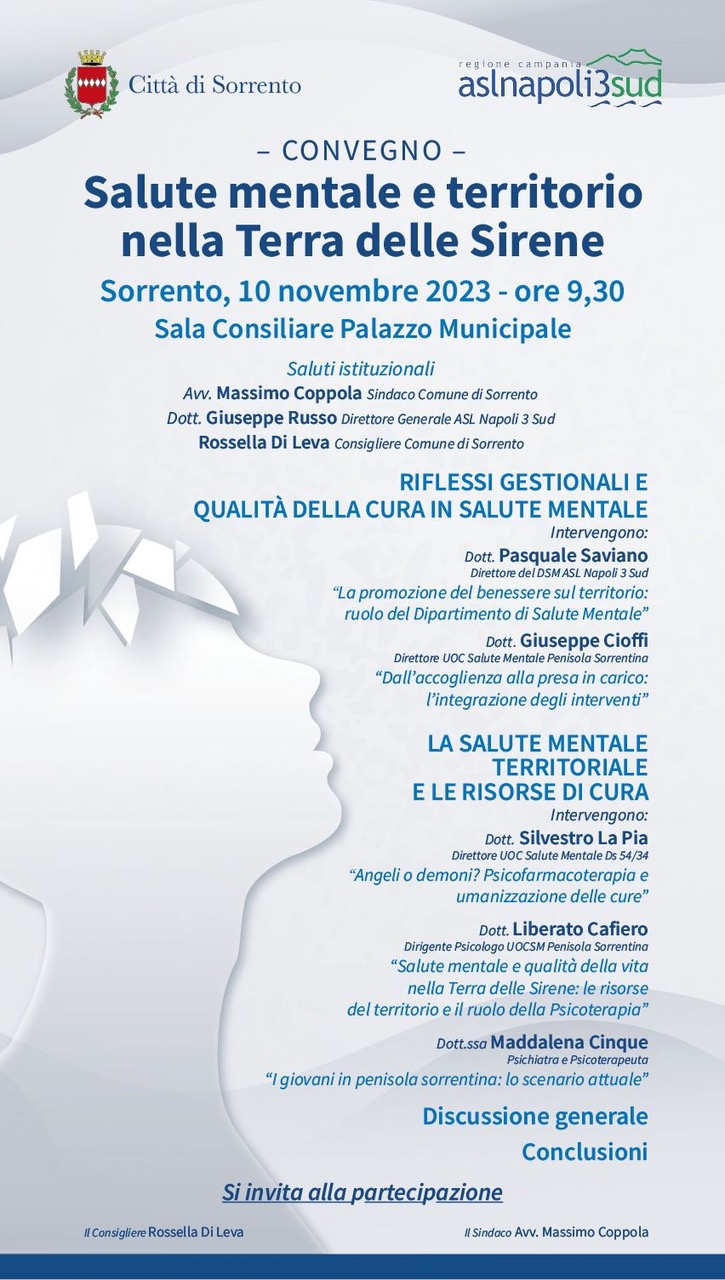

Sorrento

Sorrento

Sorrento

Presso la sala consiliare del Comune di Sorrento, si terrà un incontro sul tema "Perché tanti cesarei?".

Dopo i saluti del sindaco Massimo Coppola, l'intervento del professore Mariano Iaccarino, specialista in Ginecologia ed Ostetricia, Liberato Cafiero, dirigente psicologo presso l'Unità Operativa[...] Vai all'evento

Sorrento

Sorrento

Sorrento

Sorrento

Sorrento

Sorrento

Sorrento

Sorrento

Sorrento

Sorrento

Sorrento

Sorrento

Sorrento